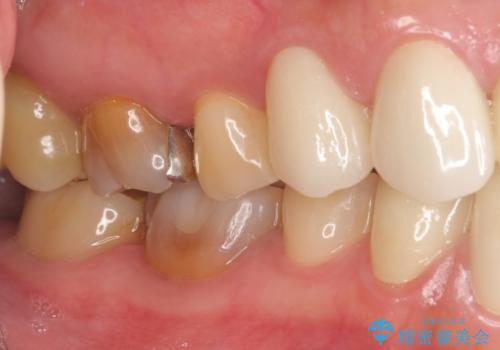

上顎は左側 4 番目から右側 4 番目までの 8 歯をオールセラミッククラウンで補綴しました。

下顎は左側 4 番目から右側 4 番目までの 8 歯と左下 567 ブリッジをオールセラミッククラウンで補綴し、右下67の銀歯はセラミックインレーによる修復を行いました。